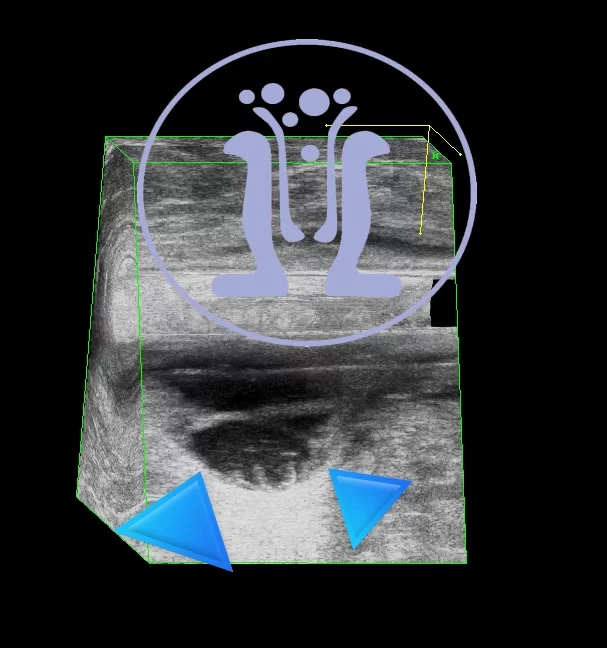

38 χρονών εύσωμος ασθενής με πόνο και πυρετό από μία εβδομάδα. Επαιρνε αντιβίωση αλλά δεν καταφερε ούτε να κουκουλώσει την φλεγμονή. Το ενδοπρωκτικό υπερηχογράφημα έδειξε μεγάλο απόστημα στην 12η ώρα. Ο ασθενής υποχρεωτικά πήρε νάρκωση. Παροχετεύθηκε μεγάλο απόστημα και τοποθετήθηκε σωλήμας παροχέτευσης. Αυτός αντικαταστάθηκε με ράμμα seton μετά μία εβδομάδα.